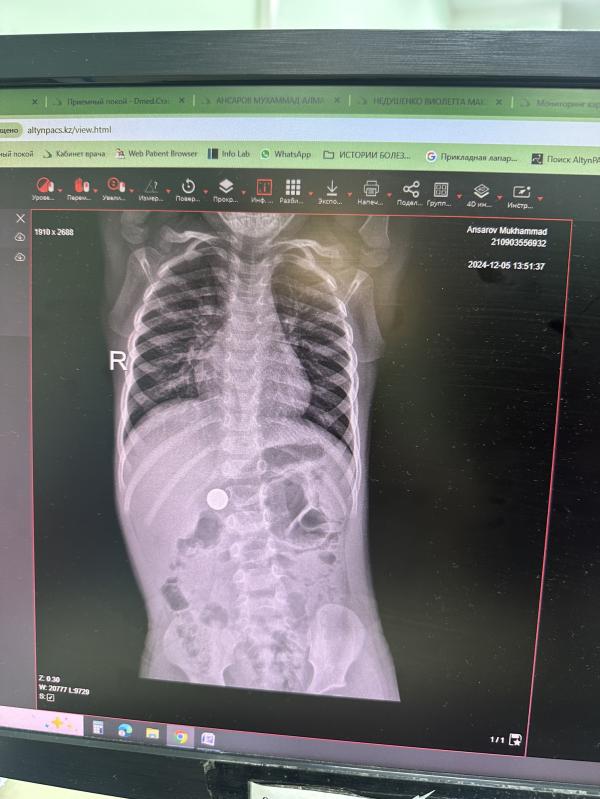

Ну и история года , как мой сын проглотил магнит от этой игрушки . Всё хорошо , но стресса было полный вагон

Да , у нас оказалось не страшно так как один , он сам вышел в туалет . Очень опасные шарики , в больнице сказали что 10-15 детей в день с этими магнитами поступают